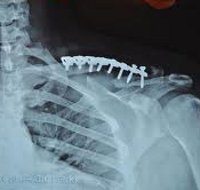

Остеосинтез ключицы

Остеосинтез ключицы выполняется при свежих и старых переломах с вывихом. Операция проводится под общим наркозом в травматологическом отделении на спине. В некоторых случаях травматолог проверяет положение фрагментов и положение металлической структуры с помощью трубки-усилителя изображения. Используйте продольный разрез. После удаления сгустков крови и промывания раны фрагменты сравнивают и фиксируют с помощью металлической структуры. Тип блокировки выбирается с учетом характеристик разрушения. Рана ушита, дренирована. В послеоперационном периоде лечение проводится в стационарных условиях, после снятия швов пациент выписывается для амбулаторного наблюдения.

После остеосинтеза ключицы.

В раннем послеоперационном периоде необходимо стационарное лечение. Иммобилизация проводится с использованием повязки Deso или гипсовой повязки на груди. После остеосинтеза проверьте рентгенограммы. Дренаж удаляется через 24-48 часов. Швы снимаются на 10-12 дней с последующим амбулаторным наблюдением. Через 3-4 недели проведите еще одну контрольную рентгенографию. Затем разрешите активное и пассивное движение конечностей.